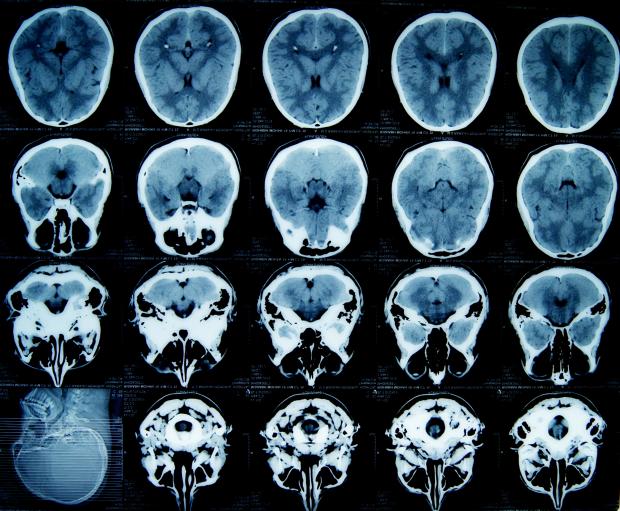

Technology has revolutionised medicine in the past century. We now have imaging methodologies like X-rays, Computed Tomography (CT) scans and Magnetic Resonance Imaging (MRI) allowing us a look inside the body without cutting it open. Nanotechnology seems poised to write the next chapter of this revolution, with various applications in biomedical imaging, diagnosis and effective treatment of diseases. In yet another advancement in this direction, an interdisciplinary team of scientists from Materials Engineering Department and Department of Microbiology and Cell Biology at the Indian Institute of Science (IISc), Bangalore, have synthesised iron nanoparticles without any oxide cover that could be used to enhance the sensitivity of MRI by producing images with better contrast. They have also demonstrated the potential application of this research in the targeted delivery of medicines and other biological molecules to specific organs in the body.

MRI works on the principle of Nuclear Magnetic Resonance (NMR) and does not use harmful ionising radiation like X-rays. Instead, it takes advantage of the magnetic properties of hydrogen atoms present abundantly in our body as a constituent of water and fat. The nuclei of hydrogen atoms behave like little bar magnets. During MRI, a very strong magnetic field is applied which aligns the spins of hydrogen nuclei. A short duration radio frequency (RF) pulse is subsequently applied which disrupts the spin alignment and tips the direction of some spins in the opposite direction. Once the RF pulse ceases, nuclear spins relax back to the original aligned position.

The energy loss during relaxation generates signals that are captured by the detectors and are processed into images. The relaxation processes are governed by microscopic energy interactions between molecules and small fluctuations in the magnetic field surrounding the water molecules. Hence, relaxation time of nuclei and consequently, brightness levels of the tissues in the MR image vary with their type, composition and location, allowing different regions to be distinguished.

The sensitivity of MRI can be improved by increasing the contrast between different types of tissues. For this purpose, magnetic contrast agents - magnetic metal ions or nanoparticles - are administered either orally or by injection into the blood stream, depending on the body part to be imaged. Since the contrast agents are themselves magnetic, they produce disturbances in the magnetic field around them, thus altering relaxation rates of the nuclei in their proximity. Several contrast agents based on gadolinium and iron oxide nanoparticles are used clinically.